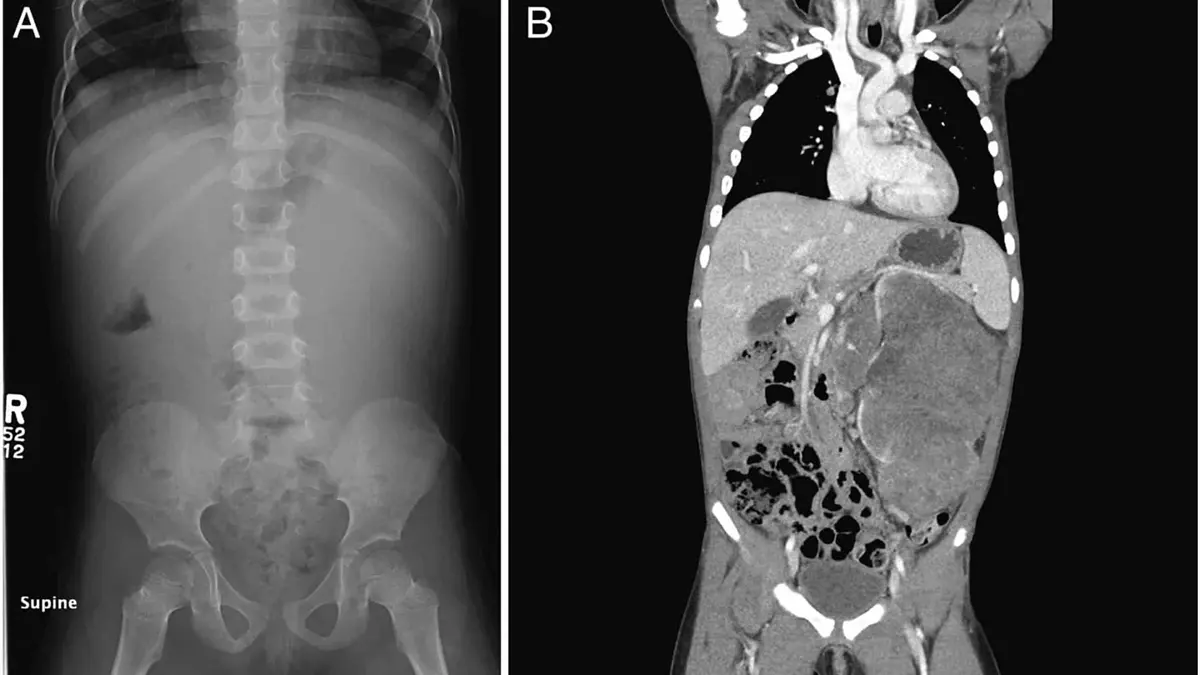

Por otra parte, el tumor se detecta por la presencia de un bulto durante una exploración de rutina. También se puede realizar una ecografía o una tomografía computarizada del abdomen para determinar la naturaleza y el tamaño del mismo.